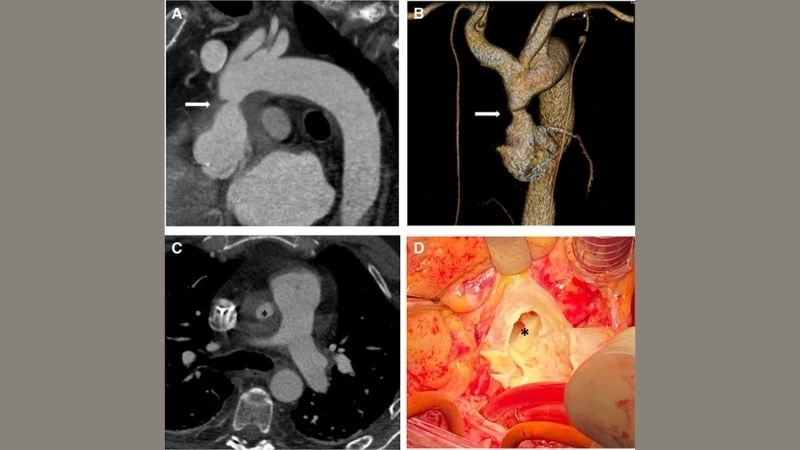

Infectious aortitis and dangerous microbial threats